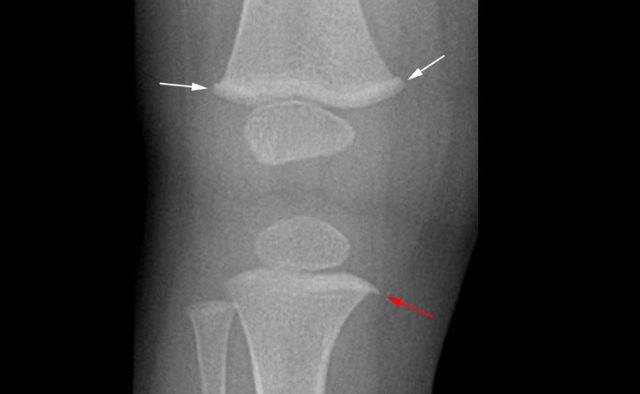

Corner fracture

The metaphyseal corner fracture, also dubbed by Kleinman as the classic metaphyseal lesion, was first described by Caffey who noted these peculiar fractures in children with subdural hematomas. They are often bilateral and in the distal tibia seen more often at the medial side.

When a small piece of bone is avulsed due to shearing forces on the fragile growth plate it is seen as the typical corner fracture. These fractures are most common in the tibia, distal femora and proximal humeri. They are frequently bilateral.

These fractures are often subtle, and the likelihood of detection is directly related to the quality of the radiologic studies.

It is for this reason that skeletal surveys in cases of suspected child abuse must be performed with utmost attention to the quality of the radiographs.

Bucket handle fractures

Bucket handle fractures are essentially the same as corner fractures.

The avulsed bone

fragment is larger and seen 'en face' as a disc or bucket handle.

Images

Bucket handle fracture in proximal tibia. The metaphyseal fracture fragment is seen as a disk or bucket handle.

Image

1.5 year-old-boy with accidental spiral fissure of the left femoral

shaft. Initially, the metaphyseal collar (white arrows) and metaphyseal spur

(red arrow) were interpreted as torus fractures and metaphyseal avulsion

fracture, respectively.

This raised suspicion for non-accidental injury. However, these are normal variants.